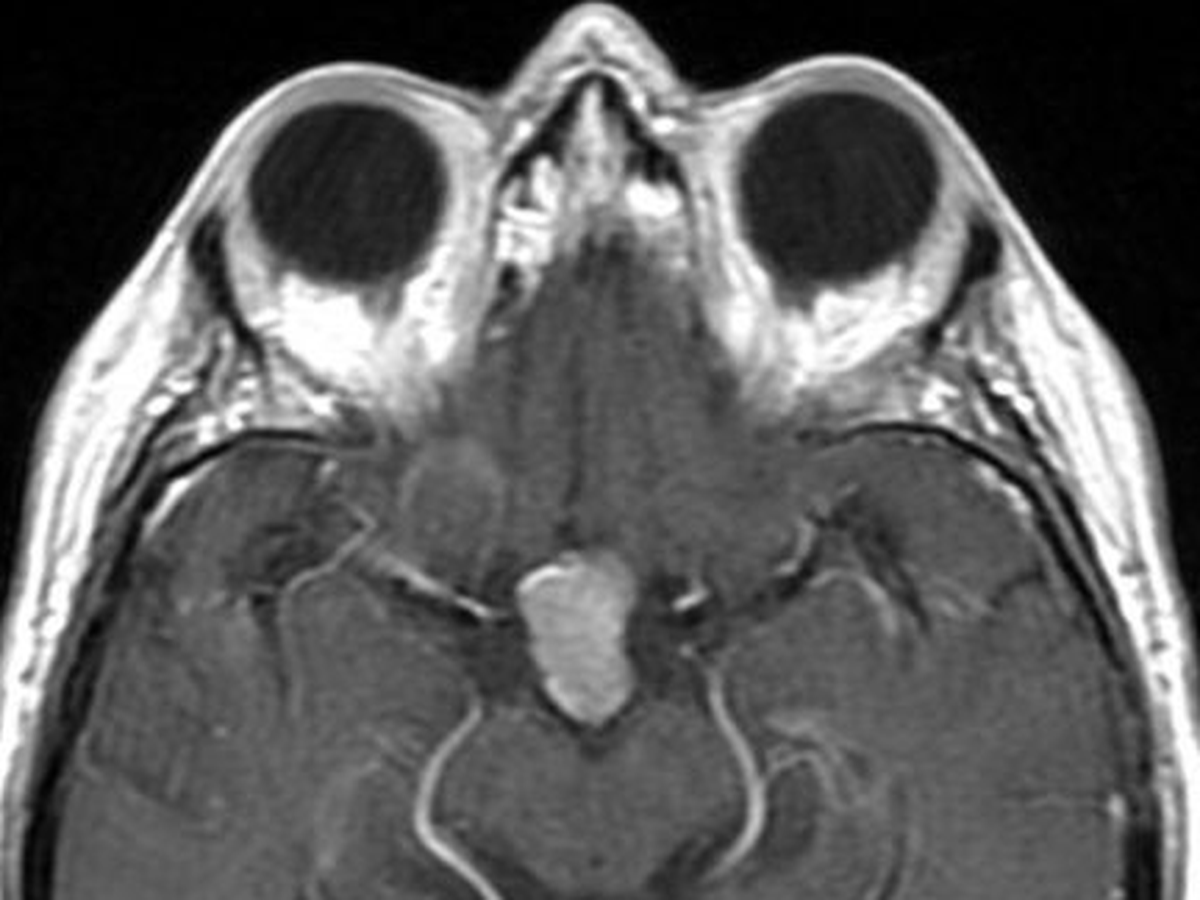

KC is currently undergoing Radiation Therapy three times a week to shrink her growing brain tumors. In April 2025, we found out that the tumor on Kc’s pituitary gland had grown from 2.3 cm to 10.5 cm. Due to her tumor being larger than 2.0 cm, Kc is ineligible to receive a Transnasal Transsphenoidal Surgery (less invasive surgery that removes brain tumors via the nose versus removal directly through the cranium). Kc silently continues to struggle mentally, physically, and financially, always placing others and their needs and wants above her own. Medication management and Radiation Therapy to shrink her tumors were recommended as the best modality of treatment. Unfortunately, Kc is not responding to treatment as doctors had hoped. Kc will need to undergo brain surgery once Radiation Treatment ends (last Radiation Treatment date: September 5, 2025) to remove the tumors from her brain.